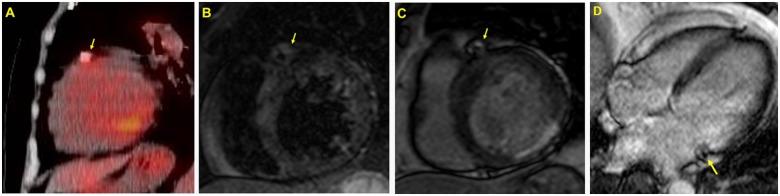

An 81-year-old woman presented with ST-elevation acute inferior myocardial infarction. Primary percutaneous coronary intervention was performed for the culprit lesion in the left circumflex artery with a permanent polymer everolimus-eluting stent (PP-EES), followed by BP-SES implantation in the left anterior descending artery. Eight months later, coronary angiography showed total occlusion of the PP-EES and diffuse ISR in the BP-SES, treated with a paclitaxel-eluting balloon. Fluorodeoxyglucose with positron emission tomography showed increased uptake around the BP-SES, and cardiac magnetic resonance imaging revealed a late gadolinium-enhanced area around both stents. Four months later, she developed re-ISR in the BP-SES, and optical coherence tomography demonstrated diffuse-layered neointimal hyperplasia with microvascularization and peri-strut low-intensity area. She was successfully treated with coronary artery bypass grafting.

一名81岁女性因ST段抬高型急性下壁心肌梗死就诊。对左旋支罪犯病变行急诊经皮冠状动脉介入治疗,植入永久聚合物依维莫司洗脱支架(PP-EES),随后在左前降支植入BP-SES。8个月后,冠状动脉造影显示PP-EES完全闭塞,BP-SES出现弥漫性ISR,遂采用紫杉醇洗脱球囊治疗。正电子发射断层扫描氟脱氧葡萄糖显示BP-SES周围摄取增加,心脏磁共振成像显示两个支架周围均有延迟钆增强区域。4个月后,她的BP-SES再次出现ISR,光学相干断层扫描显示弥漫性分层内膜增生伴微血管化和支架周围低强度区域。她最终成功接受了冠状动脉旁路移植术治疗。